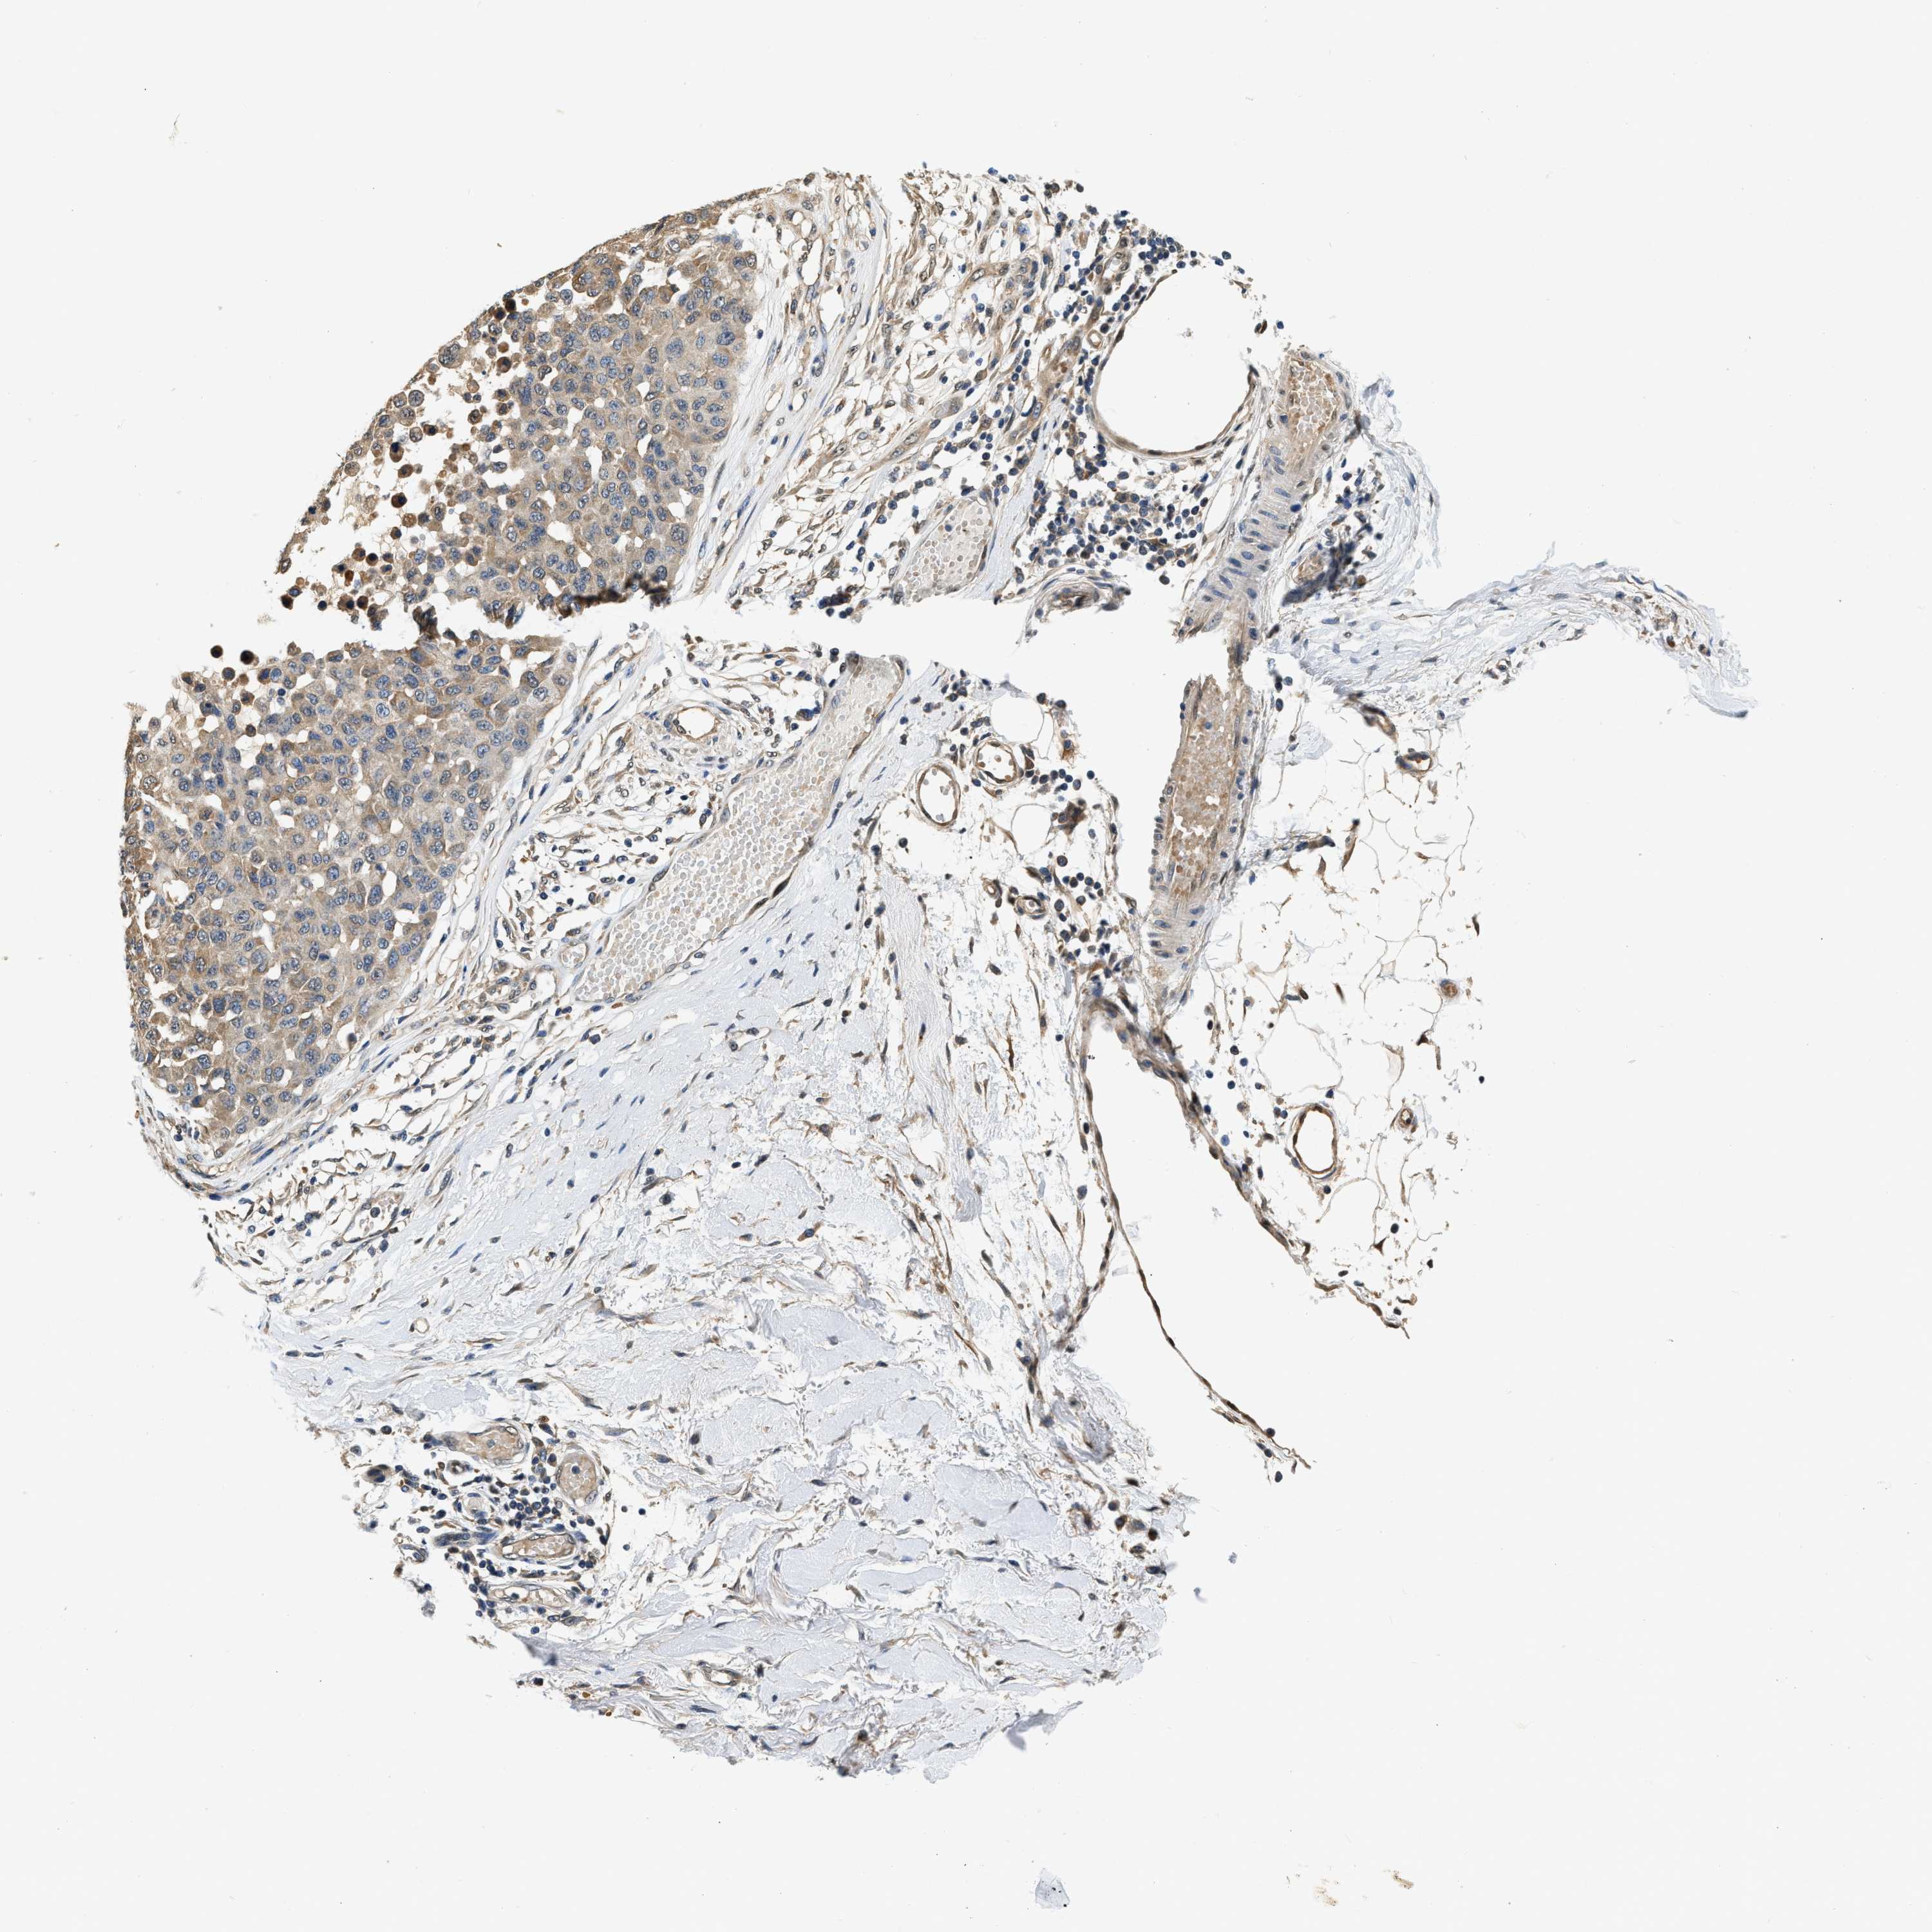

MELANOMA - Protein expressioni

A mouse-over function shows sample information and annotation data. Click on an image to view it in a full screen mode. Samples can be filtered based on level of antibody staining by selecting one or several of the following categories: high, medium, low and not detected. The assay and annotation is described here.

Note that samples used for immunohistochemistry by the Human Protein Atlas do not correspond to samples in the TCGA dataset.

Antibody stainingi

Antibody staining in the annotated cell types in the current human tissue is reported as not detected, low, medium, or high, based on conventional immunohistochemistry profiling in selected tissues. This score is based on the combination of the staining intensity and fraction of stained cells.

Each image is clickable and will lead to virtual microscopy that enables deeper exploration of all samples and also displays staining intensity scores, fraction scores and subcellular localization as well as patient and tissue information for each sample.

Antibody HPA018676

Staining

High

Medium

Low

Not detected

Intensity

Strong

Moderate

Weak

Negative

Quantity

>75%

75%-25%

<25%

None

Location

Nuclear

Cytoplasmic/membranous

Cytoplasmic/membranous,nuclear

Malignant melanoma, NOS

Malignant melanoma, Metastatic site